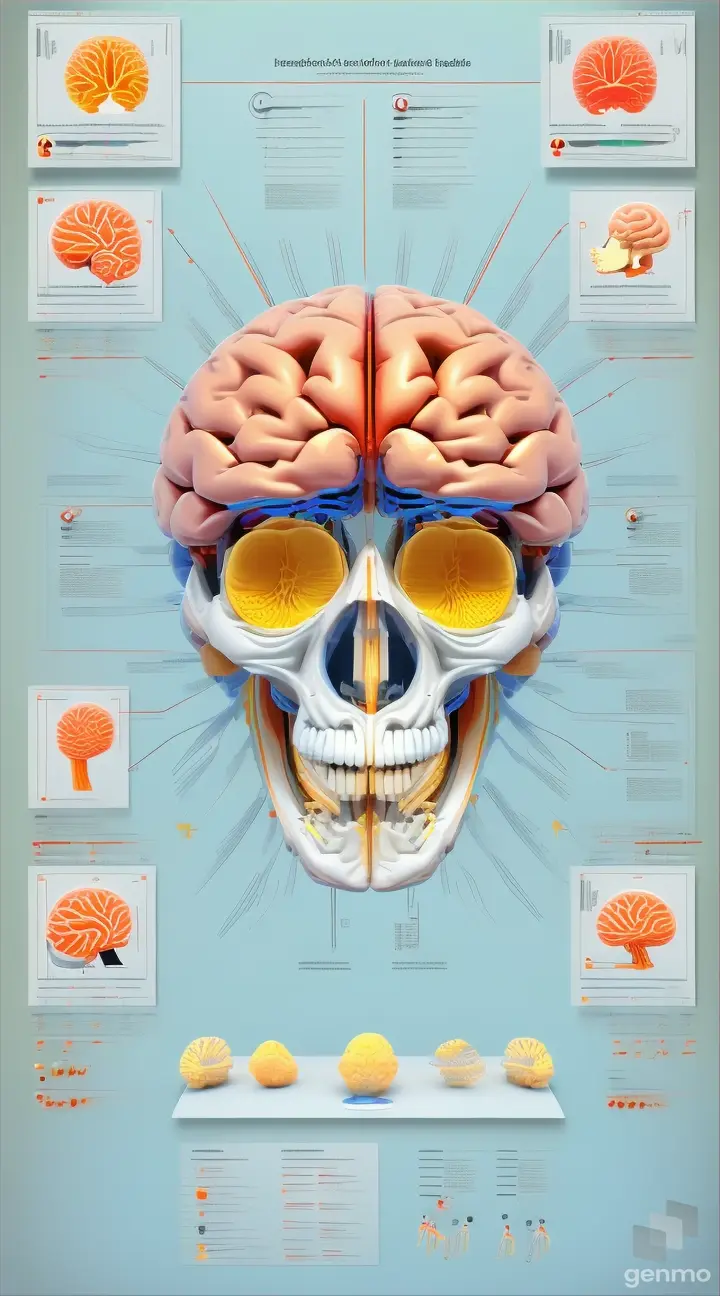

Prehistoric diet: Graphic representation of the types of food consumed by Tyrannosaurus rex, including meat, bones, and plants, based on scientific research.